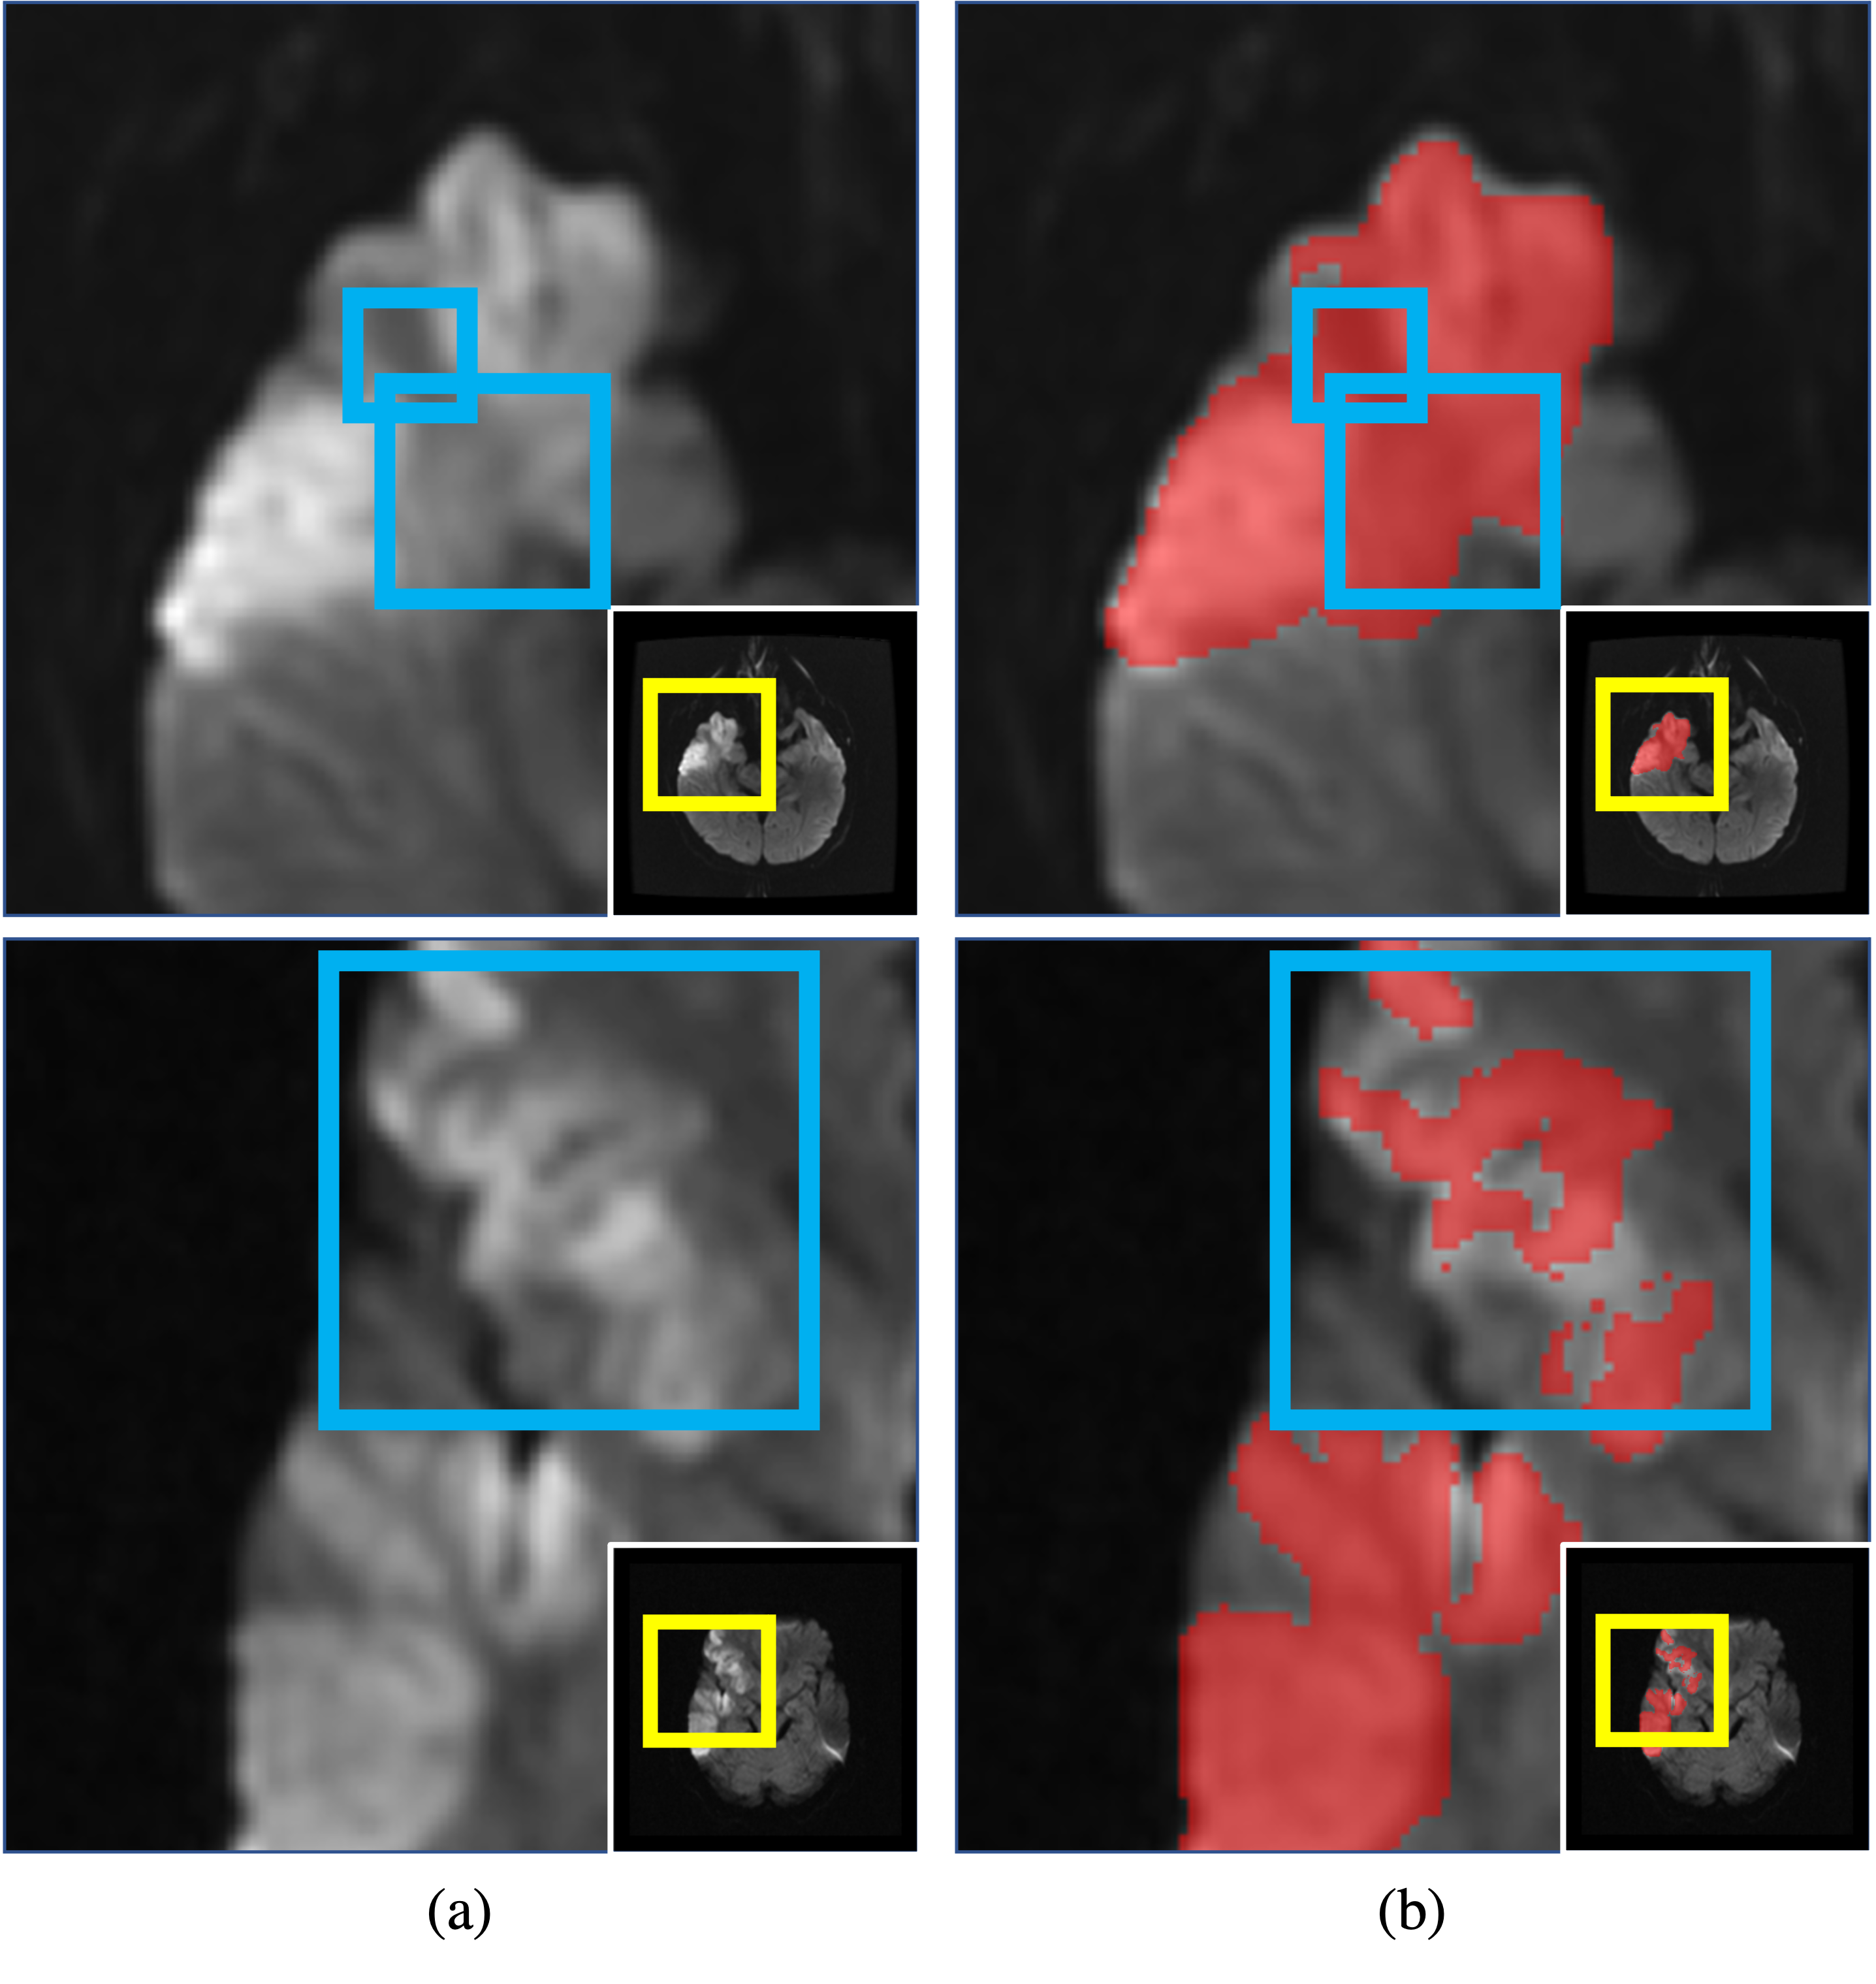

Figure 1: Human annotations on ambiguous stroke lesions. Ambiguous areas (blue squares) in the top and bottom rows caused by the same pathological variability and the partial volume effect were annotated differently. The images are sliced and zoomed from 3D images shown in the right-bottom corners for visibility.

In many applications, especially in medicine, the polarized segmentation probability is often not desirable because there are many factors that cause the inherent ambiguity in annotations even for experienced human experts, e.g., the partial-volume effect, the continuous lesion infarction process, or annotator fatigue [11, 33, 42, 65, 59, 6, 2, 56]. Fig. 1 (b) shows the examples of the human annotations of ambiguous stroke lesions in two diffusion weighted images (DWIs, Fig. 1 (a)) [14]. Ambiguous lesion areas (blue squares) caused by the lesion diffusion in the image at the top row were annotated by a human expert while not annotated in another image at the bottom row.